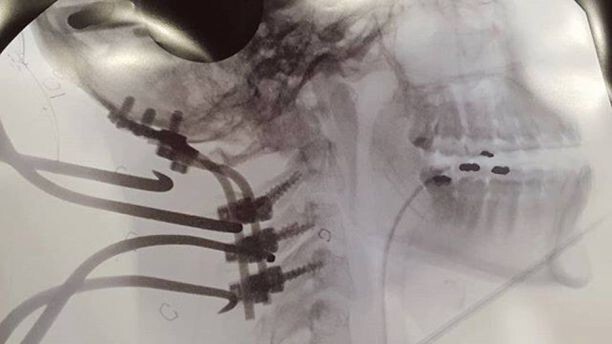

Счастливчик Марек смог выбраться и вернуться в лагерь, а за Магдаленой прислали спасателей. Девушку нашли только наутро и с раздробленной шеей доставили в больницу на четырехчасовую операцию. В результате ей установили металлические стержни и пластины. Но удивительно уже то, что она вообще выжила после такого страшного падения и ночи на льду. По словам молодоженов, беда их только сблизила. А вот путешествие придется отложить на неопределенный срок. "Это должно было стать путешествием, которое запомнится на всю жизнь. А вместо этого мы находимся в больнице", - Майкл Ванграт.